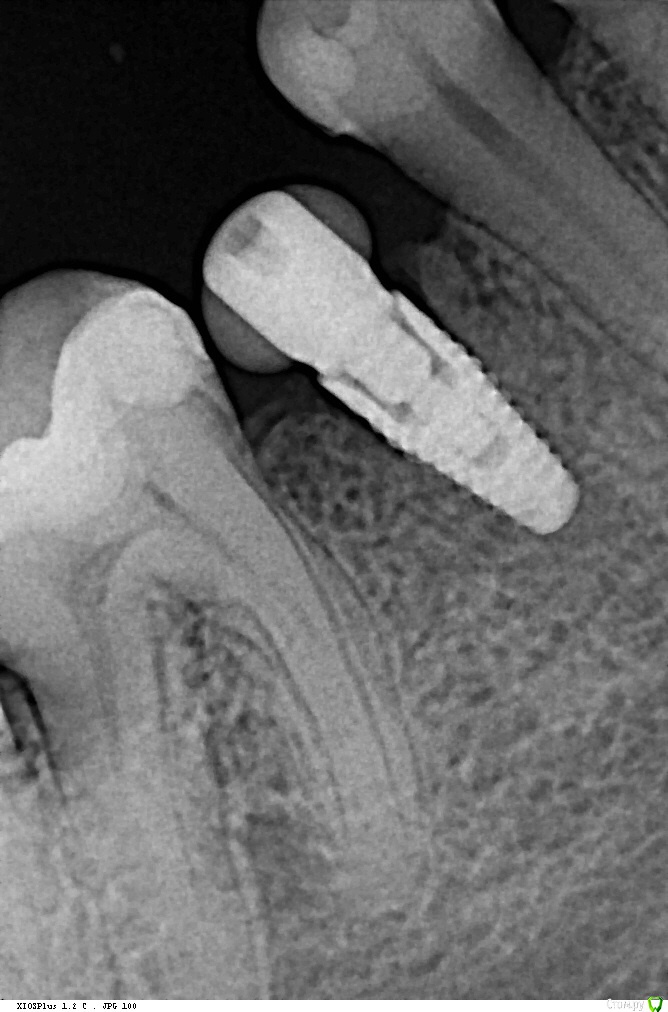

Evikrol Опубликовано 16 августа, 2016 Поделиться Опубликовано 16 августа, 2016 http://s017.radikal.ru/i438/1608/08/b97b5597a479.jpghttp://s011.radikal.ru/i317/1608/04/7613240f1e60.jpgтолько что установленный тмплантат, на одном снимке без фильтров, на другом с увеличением резкости и визуализируется щель как на ваших снимках. По этому снимите резкость и заливайте снимок. Ссылка на комментарий